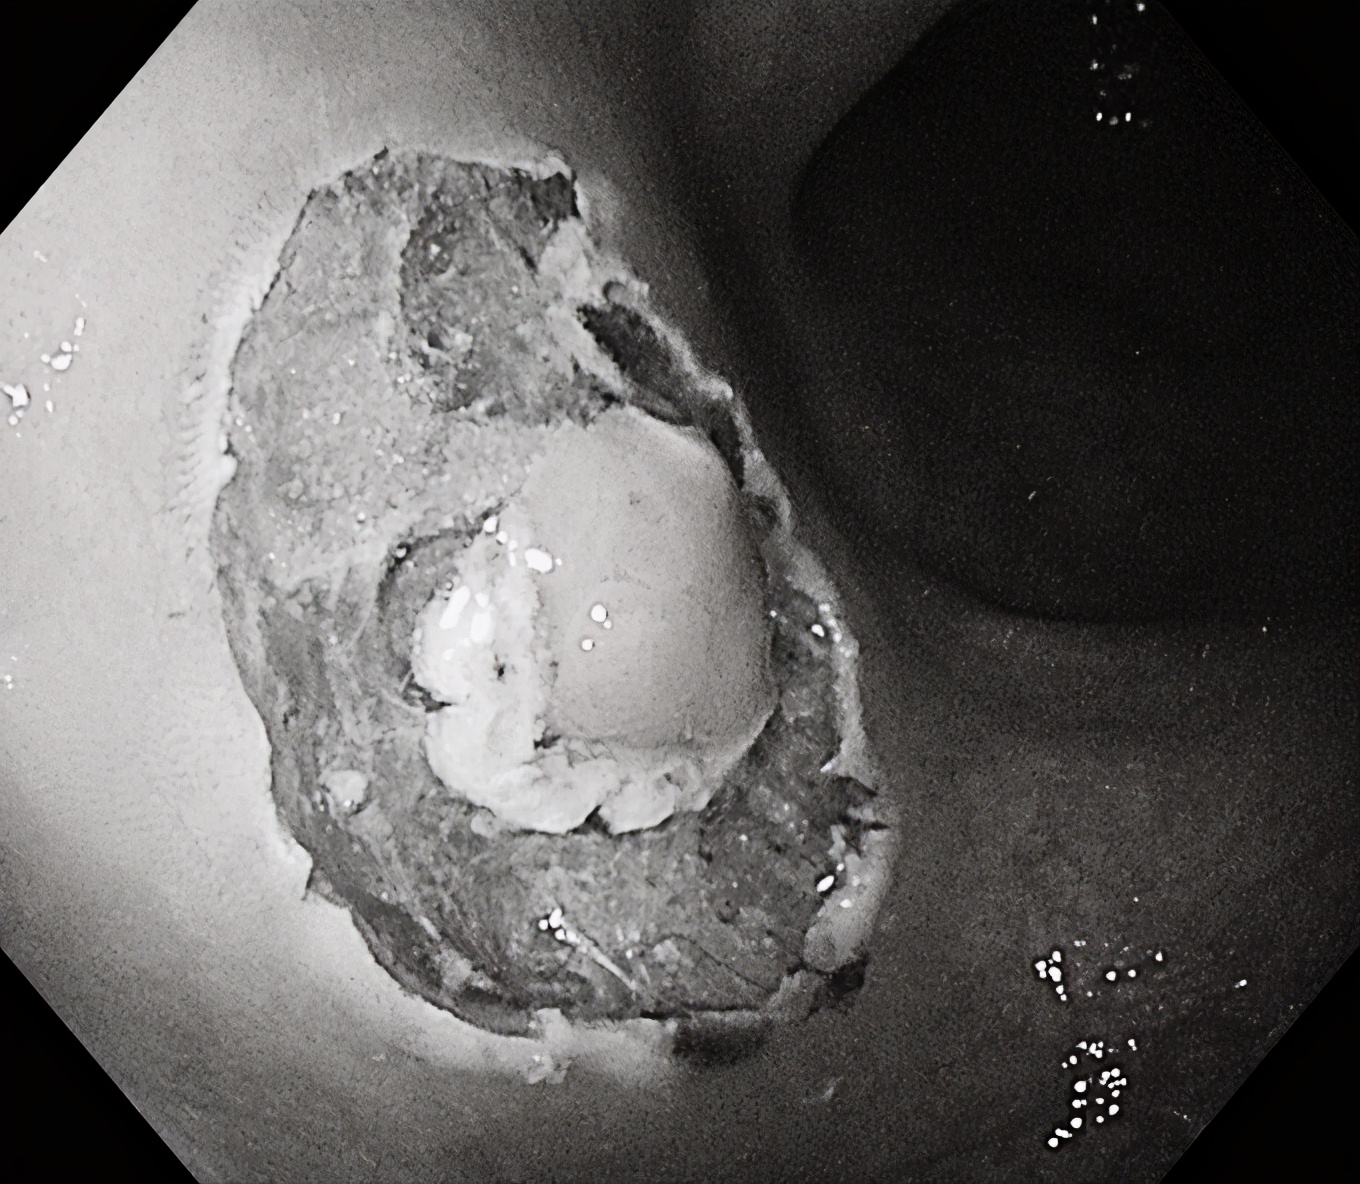

在随后一例肠镜检查中,一名中年女性患者结肠发现3枚无蒂锯齿状病变(SSL),该病变为结肠镜下极易漏诊的结肠癌癌前病变,我们用黄金刀成功施以内镜下黏膜剥离术(ESD)及内镜下黏膜切除术(EMR),完整切除结肠病变,根除了结肠癌的隐患!耗时仅仅10分钟左右,术后无并发症出现,同时送病理检查。

内镜粘膜下剥离术(Endoscopic submucosal dissection,ESD),是近年来临床对消化道早癌及较大侧向发育肿物的一项新的治疗手段,也是临床应用前景很好的技术,让更多的早期消化道癌能够在内镜下一次性完全切除,免除了器官切除等开腹手术的痛苦。ESD与剖腹手术及以往EMR等内镜治疗方法比较,具有以下优点:

对消化道早癌、巨大平坦息肉、粘膜下肿瘤(局限于黏膜肌层或黏膜下层的脂肪瘤、间质瘤、类癌等)可以应用ESD做到治愈性切除。